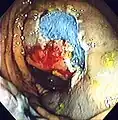

An advantage of colonoscopy over X-ray imaging or other less invasive tests is the ability to perform therapeutic interventions during the test. A polyp is a growth of excess of tissue that can develop into cancer. If a polyp is found, for example, it can be removed by one of several techniques. A snare device can be placed around a polyp for removal. Even if the polyp is flat on the surface it can often be removed. For example, the following shows a polyp removed in stages:

-

Polyp is identified. -

A sterile solution is injected under the polyp to lift it away from deeper tissues. -

A portion of the polyp is now removed. -

The polyp is fully removed.